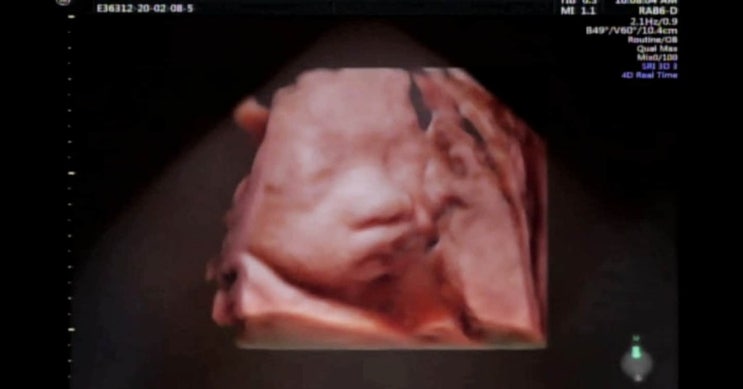

[임신일기] 33주 만삭사진 촬영하기~

집콕 생활하다 일주일만에 만삭사진 찍으러 외출!! 지난 주에는 흑백만삭사진을 찍었는데 이번엔 조리원 연...